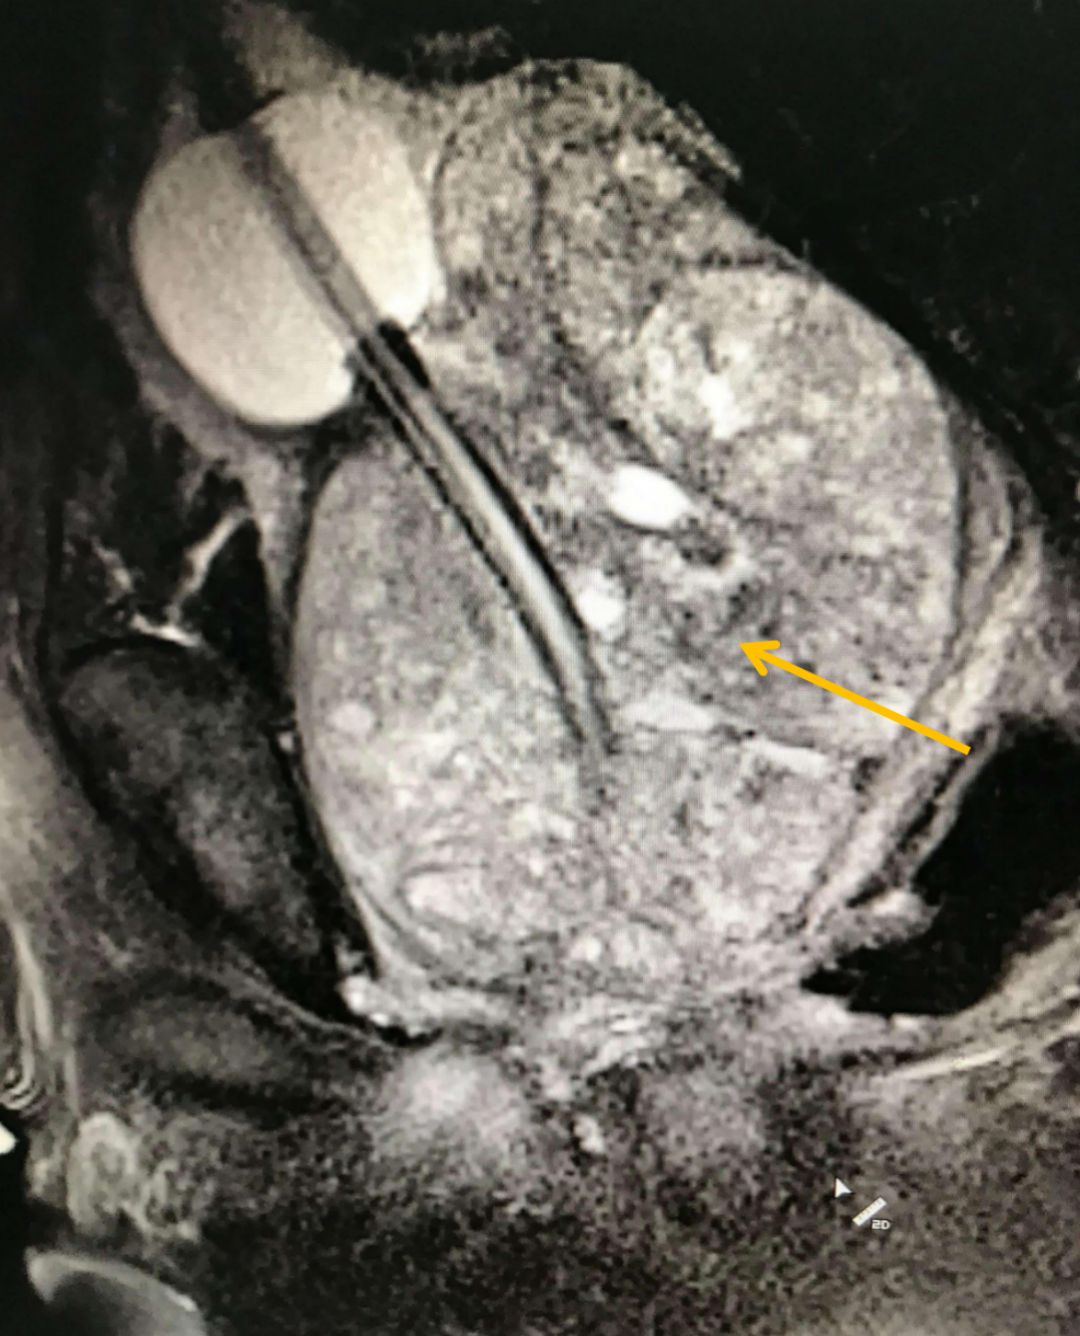

下面這張影像,展示的是一位重度前列腺增生患者的腺體——它如同一個巨大的核桃,緊緊扼住了尿道的“咽喉”??吹竭@樣的影像,我們對于他能否恢復(fù)順暢排尿,還能抱有多少期待?

圖:增生的前列腺(箭頭所指)擠壓尿道,導(dǎo)致排尿困難